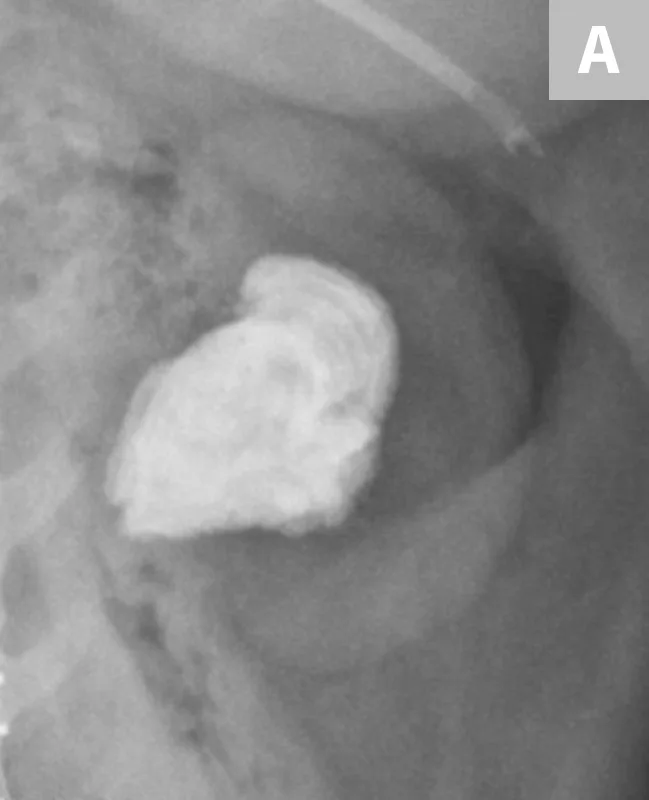

FIGURE 8A

Lateral radiograph of the urinary bladder in a dog with a confirmed calcium oxalate calculus. This calculus has a very irregular margin often seen with calcium oxalate calculus formation.